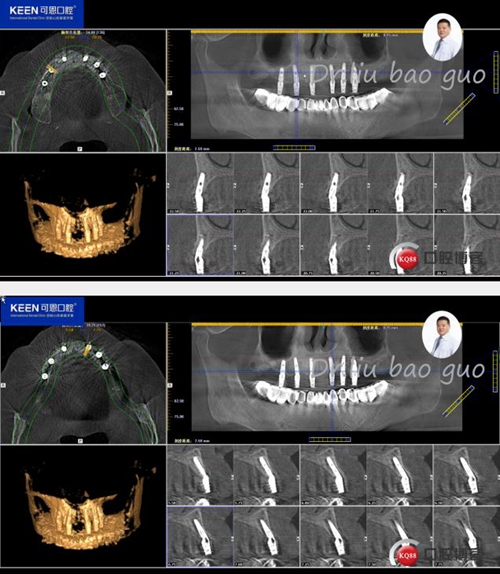

術(shù)后照片

種植后開始進(jìn)行取模,制作義齒